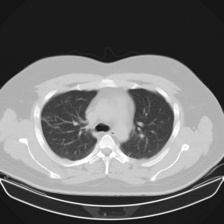

Severity Classification: Challenge to classify the involvement of lungs affected by COVID-19. This has the classes mild, moderate, severe and critical. The sampling for each of these groups can be seen in Table 1, and an example image for each of the classes is presented in Figure 3.

Figure 3: Each of the images corresponds to one of the tomography slices, with varying degrees of lung involvement by COVID-19.